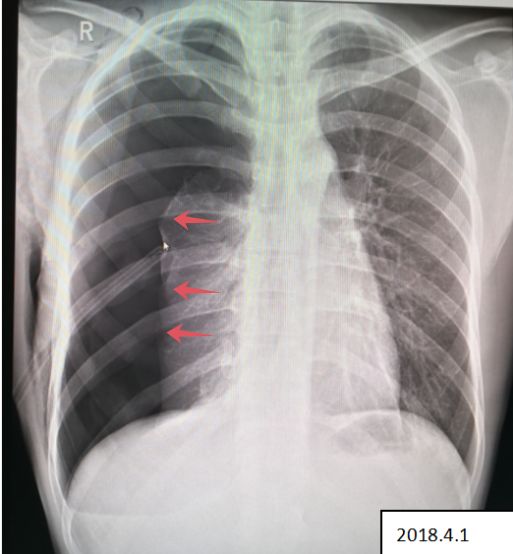

病例6患者的X线胸片

患者右侧肺野内见带状异常透亮无肺纹理区,内侧缘可见发线状被压缩肺组织外缘(红色箭头),被压缩约75%以上,两肺门影不大,肋膈角清晰、锋利,心影形态、大小正常,纵隔稍向左移位。

2018.4.1 患者复查X线图像

患者右肺气胸复查所见:右侧肺野外带(约占肺野4/5)见带状异常透亮无肺纹理区,内侧缘可见发线状被压缩肺组织外缘,被压缩约75%以上,内可见引流管置入影。 右侧胸壁可见气体影。